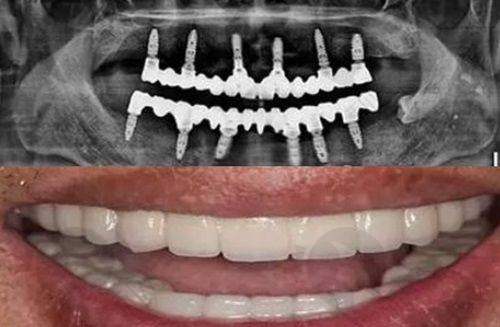

技术方面,固德熊猫口腔有两大优势。一是即刻种植技术,单颗种植只需15分钟,术后当天患者就可以佩戴临时牙冠。二是穿翼板种植技术,针对骨量不足的患者,通过植入4颗植体就能实现半口咀嚼功能,总价6.8万元(含瑞士Straumann植体)。有个真实病例,52岁的陈先生上颌骨吸收重度,通过穿翼种植技术完成了半口修复,术后3天就能正常咀嚼了。